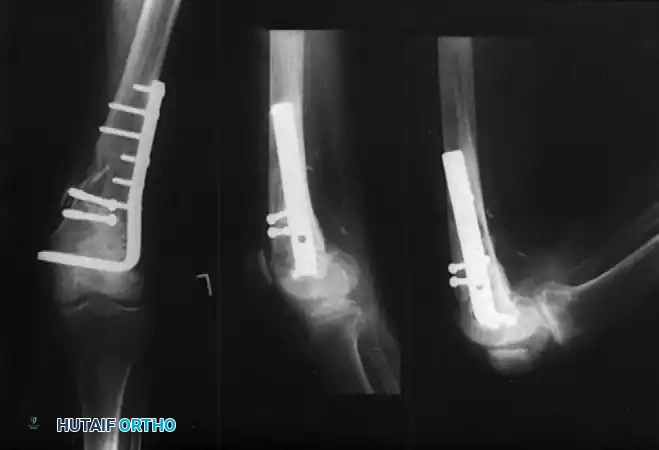

Condylar Buttress and Locked Plating Systems

For fractures with less than 3 to 4 cm of intact femoral condylar bone, or those with extensive articular comminution, traditional fixed-angle devices fail. Historically, the condylar buttress plate was utilized, allowing multiple screws to be directed into small comminuted fragments. However, without locking technology, fractures with medial comminution often collapsed into varus due to toggle at the screw-plate interface.

The Advent of Locked Plating:

The introduction of locking plate technology, specifically the Less Invasive Stabilization System (LISS) and modern Locking Compression Plates (LCP), revolutionized distal femur fracture management.

* Biomechanics: Locked screws thread directly into the plate, creating a fixed-angle construct that does not rely on friction between the plate and bone. This mitigates varus angulation even in the presence of a medial femoral defect, often eliminating the historical need for dual (medial and lateral) plating.

* Elastic Deformation: The LISS plate allows for higher elastic deformation than rigid DCS systems, acting as an internal fixator that promotes secondary bone healing via callus formation.

* Modern Implants: Newer locking implants feature polyaxial locking capabilities, allowing the surgeon to angle screws up to 15 degrees off-axis to capture specific articular fragments or avoid existing intramedullary stems in periprosthetic fractures.